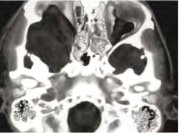

| 06:21, 3 באוגוסט 2014 | נוירוגנית4.png (קובץ) |  |

98 קילו־בייטים | Motyk | 1 | |